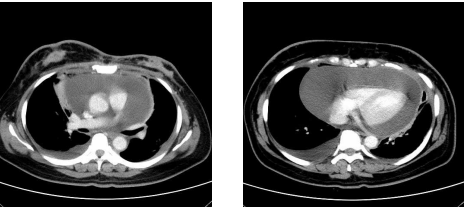

64 43 歲林先生,昨天中午和朋友去吃『鐵板燒』又喝酒。半夜感到腹痛難耐而被家人送醫。CT 顯示病 變如圖示。林先生最可能患了什麼病? (A)急性胰臟炎(acute pancreatitis) (B)胰臟腺癌(pancreatic adenocarcinoma) (C)胰臟斷裂(fracture of pancreas) (D)胰臟膿腫(pancreatic abscess)

65 一位 75 歲男性,退伍軍人,有五十多年的吸菸史,因為近五年來持續惡化的乾咳求診。身體檢查發 現有杵狀指,肺部聽診時,於兩側下半部在整個吸氣期都有緊湊的細囉音。胸部電腦斷層的影像如 附圖。此患者最可能的診斷為何?

(A)類肉瘤腫(sarcoidosis) (B)原發性肺纖維化(idiopathic pulmonary fibrosis) (C)塵肺症(pneumoconiosis) (D)慢性阻塞性肺病(COPD)